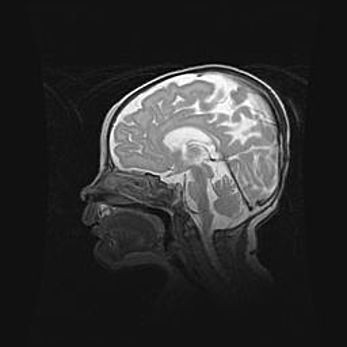

Лейкомаляция с кистозно-глиозной дегенерацией головного мозга.

Возраст: 2 месяца 25 дней

Вес: 6400 г

Окружность головы: 40 см

Срок гестации: 41 неделя

Лейкомаляцию относят к ишемически-гипоксическим повреждениям головного мозга, диагностируемым у новорожденных. При лейкомаляции в головном мозге обнаруживают очаги некроза, возникшие после тяжелой гипоксии и нарушения кровотока. В процессе морфогенеза очаги проходят три стадии: 1) развития некроза, 2) резорбции и 3) формирования глиозного рубца или кисты. Перивентрикулярная лейкомаляция (ПЛ) встречается примерно в 12% случаев среди новорожденных, обычно – у недоношенных детей, причем, частота ее зависит от массы, с которой младенец появился на свет. Наибольшее число малышей страдает лейкомаляцией, если масса при рождении 1500-2500 г.